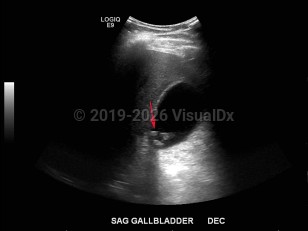

Biliary calculus

Synopsis